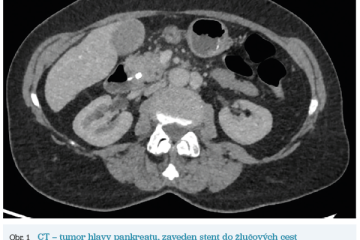

Několik studií se zabývalo AI asistovanou CT detekcí karcinomu pankreatu s AUC 0,79–0,99 %,6–8 tedy přesností porovnatelnou s přesností práce zkušeného radiologa. Stran časné detekce proběhla studie posuzující přesnost AI modelu v detekci karcinomu pankreatu v období 3–36 měsíců před prvními projevy onemocnění. Zařazeno bylo 155 pacientů s karcinomem pankreatu a 265 zdravých kontrol. AI model zde dosáhl AUC 0,98, což výrazně předčilo radiology, kteří při popisování stejných případů dosáhli AUC 0,66.9 Studie využívající DL model pro rozlišení zdravé slinivky od nálezu pankreatických neoplazií, tedy karcinomu pankreatu, intraduktální papilární mucinózní neoplazie (IPMN), serózních a mucinózních cystických neoplazií a solidní pseudopapilární neoplazie, byla prezentována s AUC 0,91, tedy opět odpovídající přesnosti popisu radiologa.10 Pro další vývoj a možné klinické využití bude potřeba přístupu k rozsáhlému archivu CT snímků karcinomu pankreatu, aby se ML modely mohly zdokonalovat. Další studie se věnovaly AI asistované diferenciální diagnostice. Ta bývá u lézí pankreatu velmi obtížná a pokrok v této problematice je tak velmi přínosný. Mezi nejzajímavější patří studie zabývající se rozlišením serózních a mucinózních cystadenomů s AUC 0,932.11 Další studie zkoumala úspěšnost rozlišení karcinomu pankreatu od zbytnění pankreatu při určitých formách chronické pankreatitidy (MFP – mass forming pancreatitis) s AUC 0,866.12 V další studii byla AI využita k rozlišení fokální autoimunitní pankreatitidy od karcinomu pankreatu s AUC 0,97.13 V rámci MR proběhlo několik studií, které se zaměřily na AI asistované zachycení a klasifikaci pankreatického karcinomu či IPMN. Studie klasifikující IPMN pomocí konvoluční neuronové sítě (CNN – convolutional neural network) byla schopna rozlišit dysplazii vysokého stupně od přítomnosti karcinomu se senzitivitou 76 %, specificitou 78 % a AUC 0,78.14 Další studie porovnávala AI modely CT a MR v predikci maligního IPMN. Výsledky ukázaly, že MR model s AUC 0,94 byl přesnější než CT model s AUC 0,864.15 S využitím PET/CT byl prozkoumán AI model rozlišující od sebe akutní pankreatitidu a karcinom pankreatu s AUC 0,9668.16 Výsledky AI v oblastech zobrazovacích metod jsou tak slibné. Dosahují minimálně přesnosti srovnatelné s radiologem a zejména v problematice časných karcinomů pankreatu člověka svojí přesností převyšují (obr. 1–5).

Vzhledem k výrazným pokrokům na poli hlubokého učení a zpracovávání dat získává AI možnost vést k transformaci klinické medicíny, jak ji známe. K lepší spolehlivosti AI také vede nárůst dostupných klinických dat, ze kterých se může učit. V rámci karcinomu slinivky břišní se další pokrok AI bude patrně zabývat časnou diagnostikou a predikcí nejefektivnějšího terapeutického postupu. Velký přínos se očekává zejména od hodnocení snímků zobrazovacích metod. Zde má velký vliv kvalita snímků a přítomnost abnormalit či jiných faktorů (například zavedených biliárních stentů), které mohou vést k nesprávným výsledkům. S nárůstem poznatků o karcinomu pankreatu bude zcela jistě růst i množství klinických dat a proměnných, proto i AI modely budou muset být vyvíjeny tak, aby zvládaly vyhodnocovat komplexní problematiku. Vzhledem k pokroku a mezioborové spolupráci bude AI zajisté velmi významným pomocníkem lékařů. Navzdory všem obtížím se tak AI patrně bude využívat ve všech aspektech problematiky karcinomu pankreatu (časná diagnostika, vymezení rizikových skupin, prognostický odhad, výběr nejlepšího terapeutického postupu, hodnocení efektu léčby).